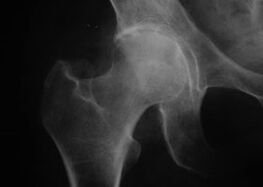

Coxatrose, artrose da articulación da cadeira

Con esta enfermidade, obsérvase un cadro clínico clásico de artrose.

O primeiro síntoma da coxartrose é a molestia na articulación da cadeira despois da actividade física.

Coa coxartrose progresiva, a dor aumenta, aparece rixidez e mobilidade limitada.

Os pacientes cunha forma grave de coxartrose aforran o membro afectado, evitando pisalo e, mentres están parados, elixen posicións nas que menos se sinta a dor.